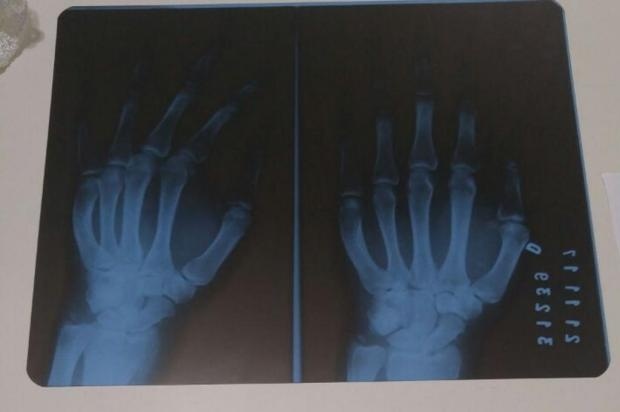

Como a dor persistia, na última terça-feira, 21 de novembro – 15 dias depois da primeira consulta – ele retornou à unidade hospitalar. O motociclista fez o exame de raios X, que indicou uma fratura no punho. Ele acreditava que, após o diagnóstico, seria rapidamente encaminhado para tratamento com o ortopedista, mas se surpreendeu ao receber a data para a consulta: dia 17 de dezembro.

Devido à lesão, a mão de Ordilão está muito inchada, dificultando as tarefas do dia a dia e ele não está conseguindo trabalhar.